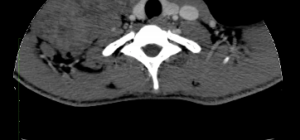

Rhabdomyosarcoma CT - Wikidoc

www.wikidoc.org

www.wikidoc.org

rhabdomyosarcoma ct wikidoc psoas muscle right heterogeneous ruslan mildly enlarged courtesy dr case source